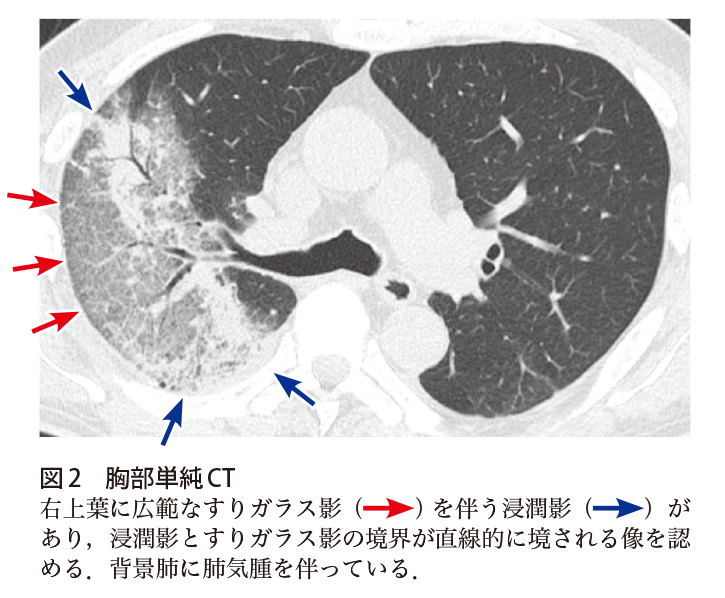

解答 解説 高熱を主訴とした60歳代男性 実践 画像診断q A 羊土社 レジデントノート 実践 画像診断q A 羊土社 レジデントノート 羊土社